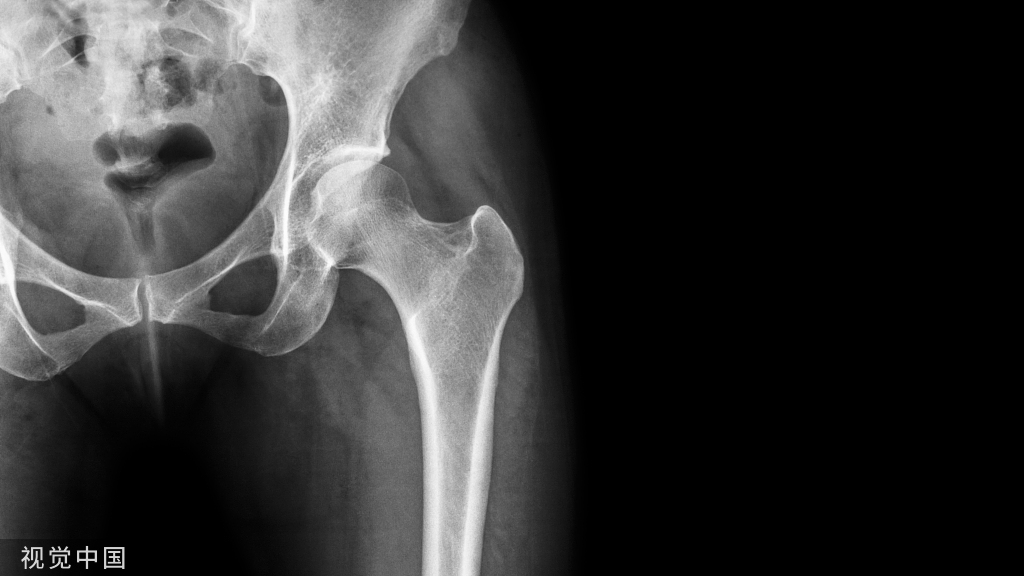

在各种运动中,腕关节都很容易受到损伤。作为关节外科医生,临床上也很容易碰上腕关节不适的病人。这时,拿到患者的影像片,你该如何判断呢?